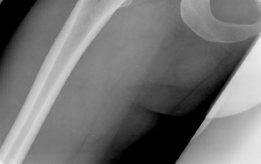

The radiographic evaluation of the dysplastic hip requires a highly standardized and rigorous protocol to accurately quantify the three-dimensional deformity. The initial assessment begins with a standing anteroposterior (AP) radiograph of the pelvis. In this patient, the AP view immediately reveals the hallmark signs of DDH: decreased anterolateral coverage of the femoral head and a broken Shenton line. The broken Shenton line—a step-off between the medial border of the femoral neck and the inferior border of the superior pubic ramus—indicates proximal and lateral migration of the femoral head due to structural instability. Furthermore, we observe an increased Tönnis angle (acetabular inclination) and a significantly reduced Lateral Center Edge Angle (LCEA) of Wiberg, confirming the diagnosis of severe lateral uncoverage.